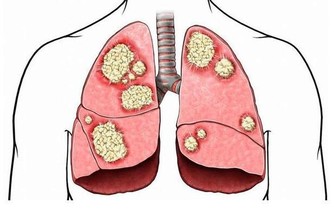

據美國紐約一家專門從事癌癥研究的權威機構透露,中國和日本婦女乳腺癌的發病率比西方低得多,這是為什麼呢?

科學家在比較了世界各國的三餐食譜後得出結論:是由於中國和日本婦女多吃大白菜的緣故。

調查資料表明,每10萬名婦女中,每年乳腺癌的發病率為:中國9人,日本21人,北歐84人,美國91人。

大白菜何來如此神功?

實驗證明,大白菜所含有的許多物質、具有防癌抗癌的作用,因此在美國國立癌癥研究所、發表的防癌食品排行榜中、將白菜排在僅次於大蒜的後面,名列第二。。